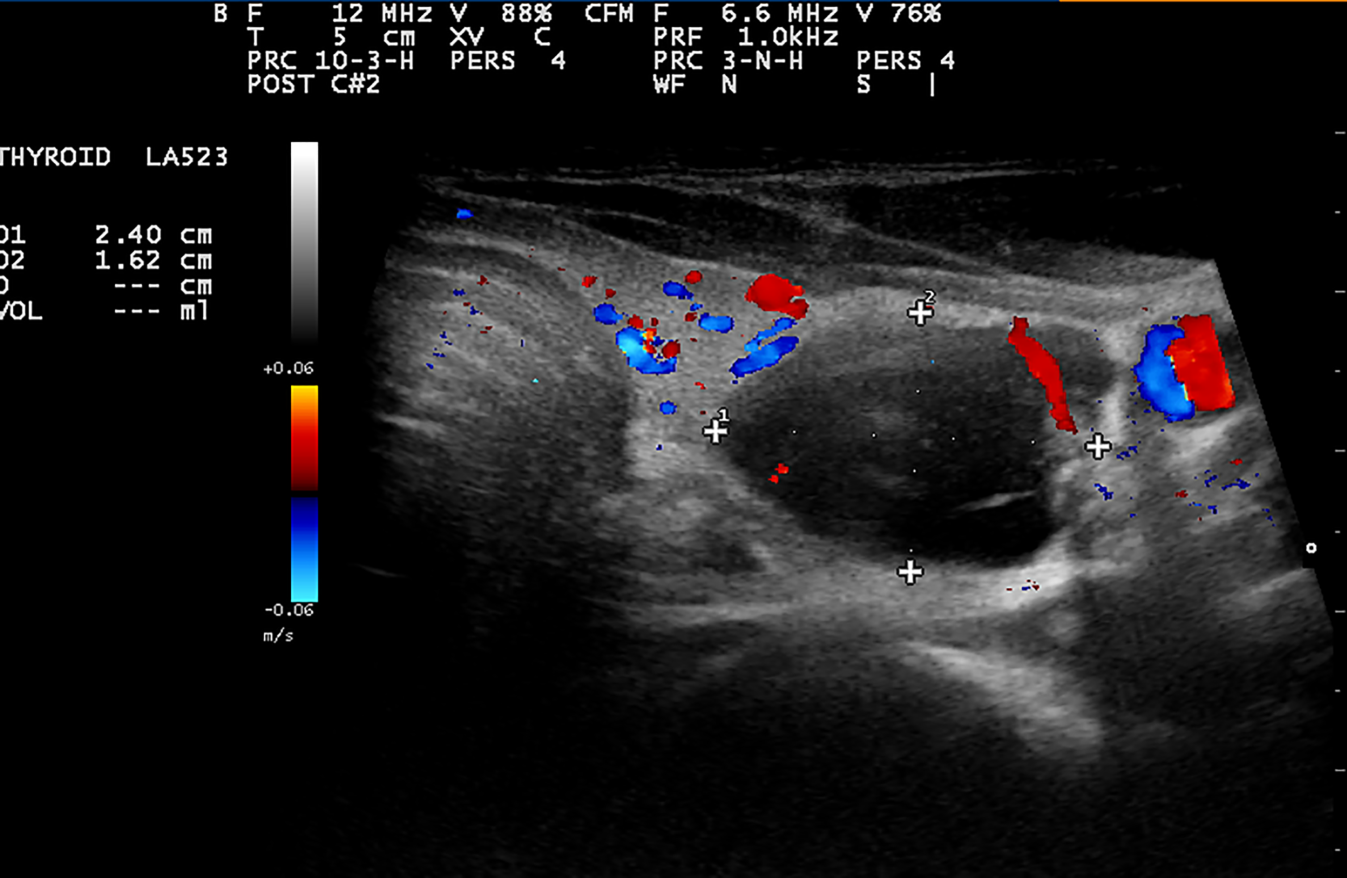

Im Rahmen einer Gesundenuntersuchung wurde bei einem 50-jährigen sonst gesunden Patienten ein 24 mm großer, hypoechogener, teilweise stark vaskularisierter Knoten im linken Schilddrüsenlappen entdeckt (Abb. 1). Auffallend war in der Läsion links eine starke Retention des Tracers im MIBI-Scan. Präoperativ war das Serumkalzium im Normbereich, allerdings wurde das Parathormon präoperativ nicht bestimmt. Das Serumkalzitonin war ebenfalls im Normbereich. Im Schnellschnitt fand sich exzentrisch im Hemithyreoidektomiepräparat ein 2,3 cm großer, partiell zystischer Knoten, welcher aus graugelb, teils grauweiß gefärbtem Gewebe mit erhöhter Konsistenz bestand. Die Entscheidung des Pathologen war Schilddrüsenkarzinom ohne genauere Spezifizierung. Folglich wurde eine totale Thyreoidektomie mit funktioneller Neck Dissection beidseits durchgeführt. Die definitive histologische Untersuchung ergab allerdings ein intrathyreoidal gelegenes Nebenschilddrüsenkarzinom pT1b, N0 (0/33), V0, L0, Pn1, R0. Die Tumorformationen zeigten abschnittsweise ein irreguläres trabekuläres Baumuster mit auch klein-solidem insulär genestetem Zellbild sowie typischerweise einer starken fibrösen Kapsel mit in die Tumorformationen reichenden Septen (Abb. 2). Der Proliferationsindex Ki67 lag im Bereich zelldichter Tumorabschnitte bei maximal 5 %. Keiner der Lymphknoten zeigte einen Tumorbefall. Bemerkenswert war, dass die normale rechte obere Nebenschilddrüse symmetrisch auf gleicher Höhe wie links das Karzinom intrathyreoidal positioniert war. Der postoperative Verlauf war völlig ungestört. Parathormon und Kalzium am ersten postoperativen Tag waren leicht vermindert, aber bei der Entlassung am 3. postoperativen Tag waren beide Parameter bereits wieder im Normbereich. Der Patient hatte keine Kribbelparästhesien. Die Stimmbandfunktion war intakt. Der Patient ist nun 4 Jahre und 3 Monate rezidivfrei!

Abb. 1

Die präoperative Sonografie zeigt links den hypoechogenen, zum Teil zystischen Knoten